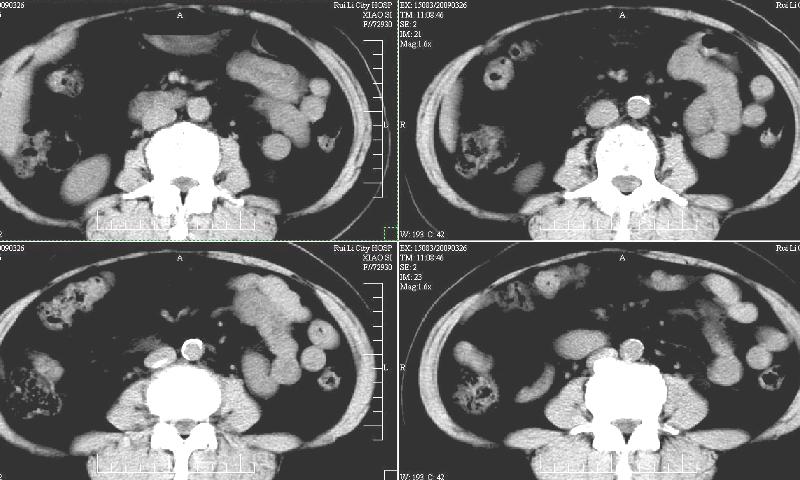

标题: CT19130:F,60岁。2008-10-17CT发现肝脏占位,现在复查! [打印本页]

标题: CT19130:F,60岁。2008-10-17CT发现肝脏占位,现在复查!

前次已经增强,所以这次没有增。ct:肝右叶平滑肌血管脂肪瘤治疗后复查,肿瘤大小同前或略有缩小。2、轻度脂肪肝。3、肝左叶小囊肿

支持楼主意见,肝右叶平滑肌血管脂肪瘤。